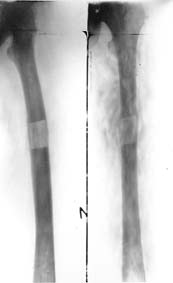

Limb lengthening and genu varum treatment

Result of the treatment.